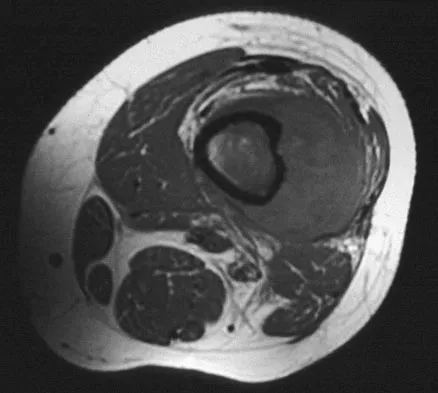

A healthy 16-year-old boy has had increasing pain in the right knee for the past 3 months. Examination reveals warmth and swelling around the distal femur. Radiographs and an MRI scan are shown in Figures 51a through 51c, and a biopsy specimen is shown in Figure 51d. What is the most likely diagnosis?

Explanation

The radiographs show a bone-producing lesion in the distal femoral metaphysis in this case of classic osteosarcoma presenting in the most common location, the distal femur. The coronal MRI scan reveals a marrow-occupying lesion with extension into the soft tissues. The histology shows osteoid production by pleomorphic cells consistent with an osteosarcoma. Ewing's sarcoma is a bone tumor characterized by uniform small blue cells on histology. Rhabdomyosarcoma is the most common childhood soft-tissue sarcoma. Osteomyelitis has an inflammatory appearance on histology. Malignant fibrous histiocytoma of bone has a lytic radiographic appearance and a pleomorphic storiform pattern without osteoid on histology. Wold LE, Adler CP, Sim FH, et al: Atlas of Orthopedic Pathology, ed 2. Philadelphia, PA, WB Saunders, 2003, p 179.